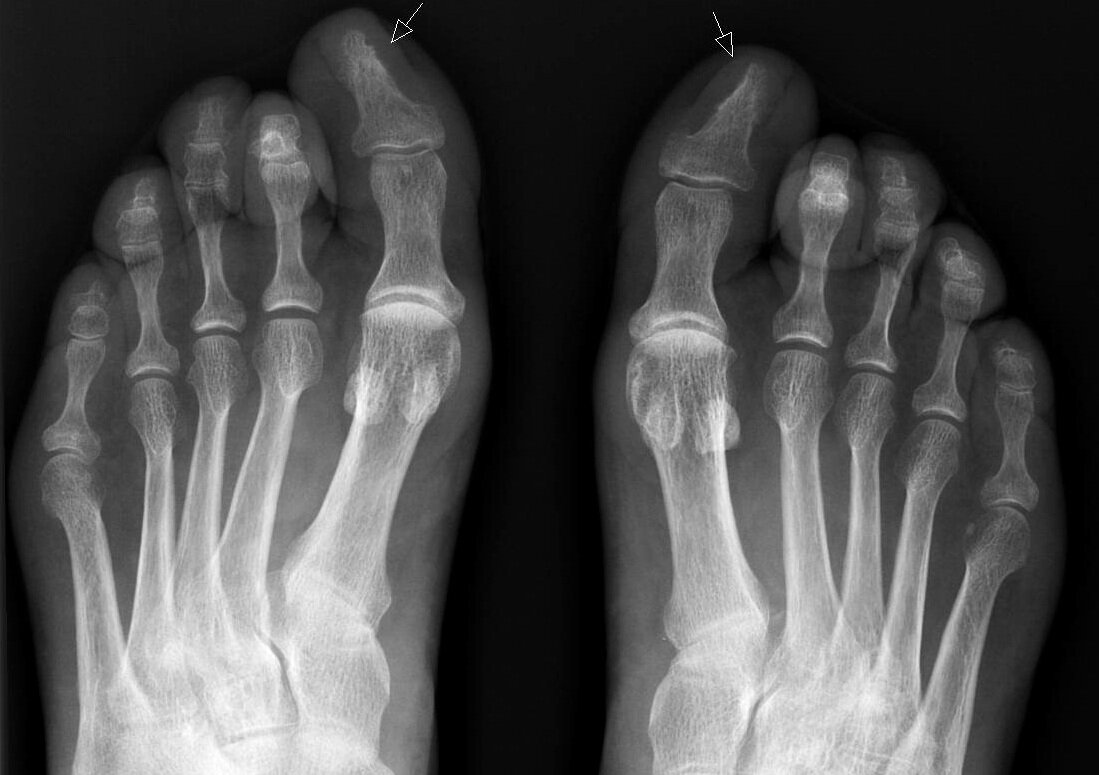

Что делать с вросшим ногтем? Профилактика и лечение

Онихрогрифоз - медицинское название врастания ногтевой пластинки в мякоть пальца.

Очень неприятные последствия и болезненные ощущения развиваются уже с первых дней появления данной патологии.

Причинами могут служить:

* Неправильное надрезание ногтей.

* Грибковые заболевания.

* Ортопедические нарушения стопы.

* Травмы пальца.

* Ношение узкой и тесной обуви.

Различают 3 стадии развития онихрогрифоза:

1. Покраснение и отек.

2. Появление гноя и крови, иногда инфекции.

3. Воспаление переходит в хроническую форму и может перейти на кость.